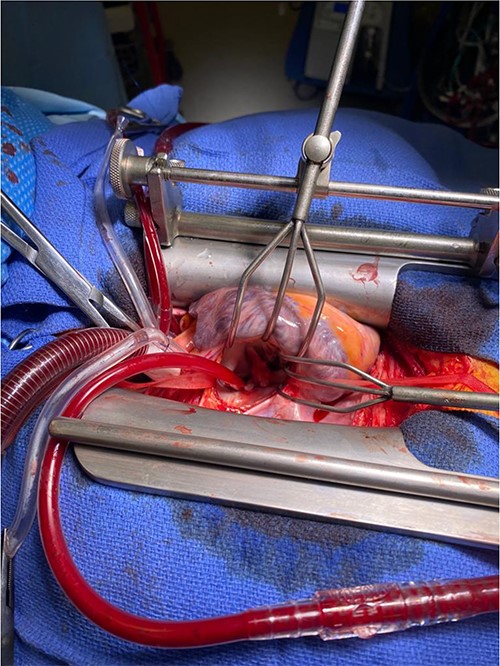

A CTPA was undertaken on Day 2, which excluded pulmonary embolism but confirmed bilateral peri-hilar consolidation and pleural effusions consistent with pneumonia. However, her pulmonary artery was dilated at 32 mm indicative of potential heart failure. On Day 5 of her ICU stay, a transthoracic echocardiogram was undertaken that revealed there to be severe mitral regurgitation including a mobile echogenic mass attached to the underside of the anterior mitral valve leaflet consistent with a vegetation (Figs 1 and 2).

Pre-operative TTE depicting mitral valve with vegetation (labelled).

Intra-operatively, femoral–femoral bypass was established and a 3 cm windsock vegetation was found with a 1.5 × 1.5 cm hole at the aortic inlet on the annular junction. The vegetation travelled from the LV to LA as shown in Figs 3 and 4. The vegetation was excised and the valve debrided, which resulted in moderate regurgitation from severe. Hence, a further 26 mm Physio II ring was placed resulting in no mitral regurgitation. The excised vegetation is shown in Fig. 5 and the post-op TTE images are shown in Figs 6 and 7.